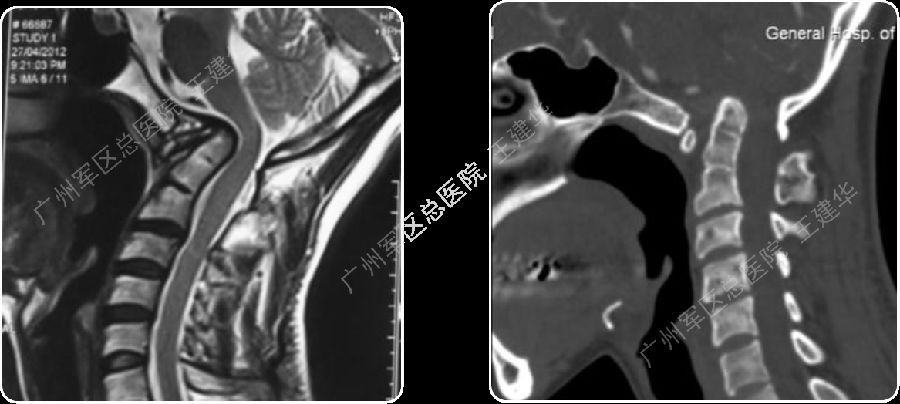

颈椎MR检查提示:颈椎上端结构陷入枕骨大孔,脑干受压变形

本例患者手术过程

手术复位过程

手术完成

手术前后对比

可以看到:

陷入枕骨大孔的寰椎和齿突已经下拉复位,枕颈排列恢复正常

脑干压迫解除,延髓脊髓角恢复正常